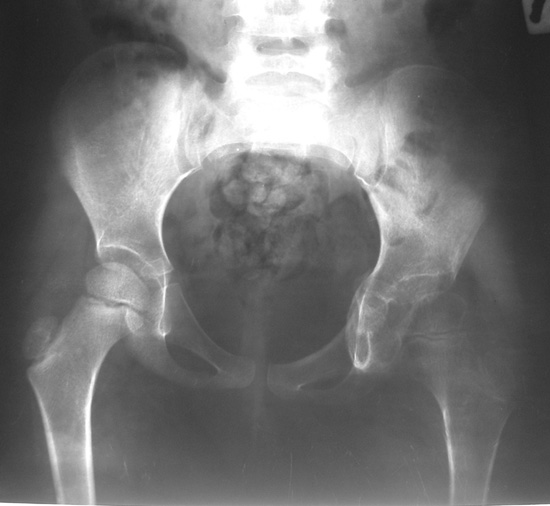

После операции ребенок находился в гонитной повязке три недели. Затем

повязка снята. На контрольной рентгенограмме выявлен вывих левого бедра.

Наложена система скелетного вытяжения за левое бедро. Через две недели

система снята, наложена шина Веленского.

Имя     : luxation after surgery.JPG

Тип     : image/jpeg

Размер  : 45474 байтов

Описание: отсутствует

Url     : http://weborto.net:8080/pipermail/ortho/attachments/20070912/e455cc09/attachment-0003.jpeg